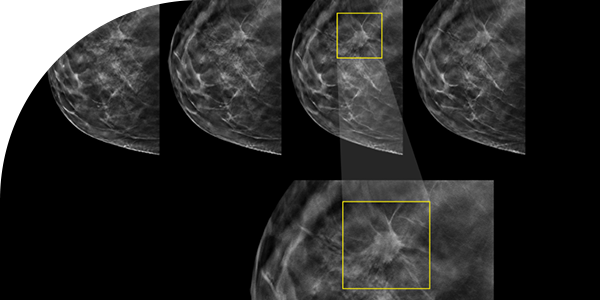

미세석회화의 정확한 분석을 위해서는 고화질의 유방촬영(Mammography)과 확대촬영(Magnification view)이 가능한 장비가 필요합니다. 블레스유여성의원은 세계적으로 인정받은 Hologic사의 Selenia Dimensions 3D Mammography 시스템을 도입하여 정확한 진단과 안전한 조직검사를 위한 3D 유방촬영 시스템과 입체정위생검(Stereotactic Biopsy) 기술을 도입한 특화된 미세석회클리닉을 운영합니다.

의심스러운 미세석회화가 발견되면 그 부위를 자세히 보는 확대촬영을 추가로 하게 됩니다. 확대촬영에서 석회화의 개수, 모양, 분포, 동반된 다른 소견이 있는지 등을 분석합니다.

미세석회화는 크기가 매우 작고(보통 0.5mm 미만) 초음파에서 잘 보이지 않아 일반적인 방법으로는 정확한 위치 파악과 조직 채취가 어렵습니다. 블레스유에서는 첨단 장비를 활용해 병변의 정확한 위치를 파악 후 바늘 삽입 위치를 결정합니다. 정확한 부위에서 조직샘플을 채취 후 목표 석회화 포함 여부를 즉시 확인합니다.

3D 영상으로 미세석회화의 정확한 위치를 파악하여 1mm 이내 정밀도로 조직 채취